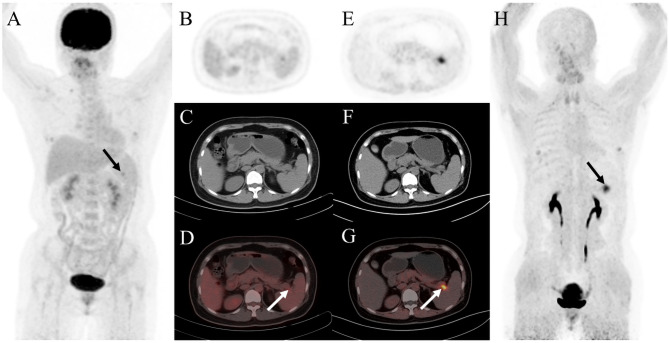

Fig. 4.

A 63-year-old woman was diagnosed with cervical squamous cell carcinoma in another hospital for more than 3 months and was referred to our hospital. Then 18F-FDG PET/CT and 68Ga-FAPI PET/CT were performed for initial assessment. The MIP image (A) and axial views of 18F-FDG PET/CT showed slightly increased uptake in cervix (B, solid arrow; SUVmax, 8.6), left sacrum (C, solid arrow; SUVmax, 2.4), and left ischium (D, dashed arrow; SUVmax, 0.8). While 68Ga-FAPI PET/CT revealed significant increased FAPI uptake in corresponding cervix (E, solid arrow; SUVmax, 12.5), left sacrum (F, solid arrow; SUVmax, 11.1), and left ischium (G, dashed arrow; SUVmax, 7.0). Subsequently, the patient received radiotherapy. It showed the left sacrum and left ischium lesion decreased in size after 3 months